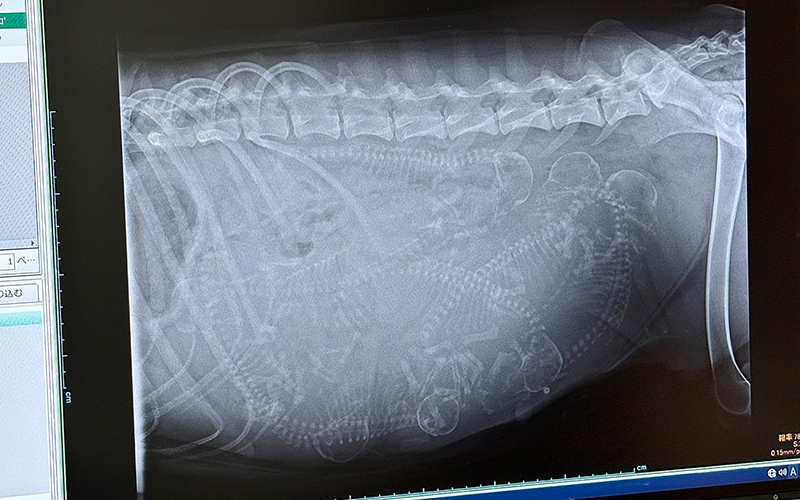

そして本日、いちごが赤ちゃんの頃からお世話になっている動物病院へ受診に行ってきました。

先生によると、出産予定日は 11月9日頃。

なんとお腹の中には 7匹 ほどの赤ちゃんがいるかもしれないとのことです!

エコーの写真を見た瞬間、胸がじーんと熱くなりました。

確かに小さな命が宿っている――その奇跡を目の当たりにし、感動でいっぱいになりました。